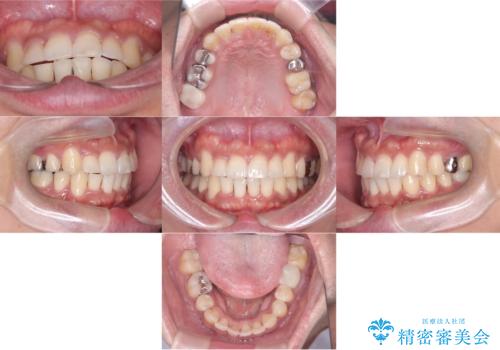

【ワイヤー矯正】八重歯と下の歯の凸凹を治したい

- 主訴:右上の八重歯と、下の歯の凸凹を治したい

上顎右側第一小臼歯と下顎右側第一小臼歯を抜歯しワイヤー矯正を行いました。

右側2級、左側1関係だったため、右側上下第一小臼歯を抜歯し、ワイヤー矯正を行いました。

期間:2年6カ月